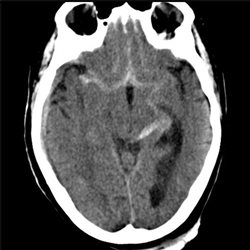

Aneurysm 02

76 yo female who had a syncopal episode and fell striking her head; now has reduced level of consciousness. There is a history of advanced cardiovascular disease. CT, CTA